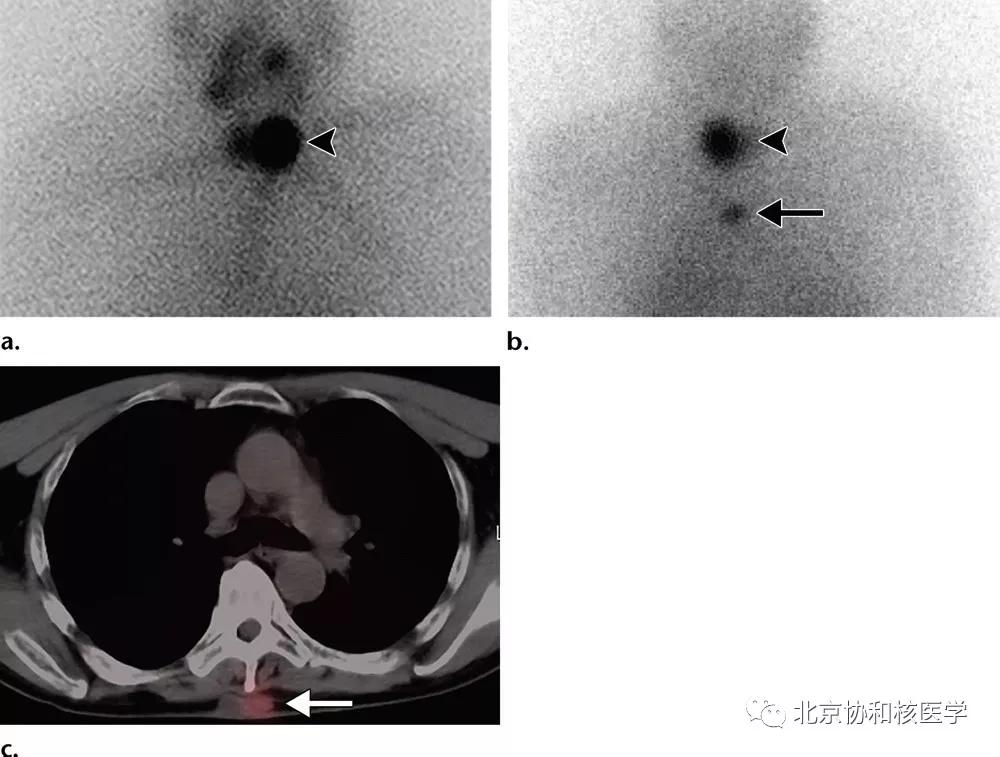

63岁女性,甲状腺癌病史,肺内不典型分支杆菌感染所致碘摄取:

肺内曲霉菌球摄取:

鼻腔脓肿所致碘摄取,其下方可见颈部残余甲状腺:

肺鳞癌所致碘摄取(后位图像),同时可见颈部甲状腺残余病灶: